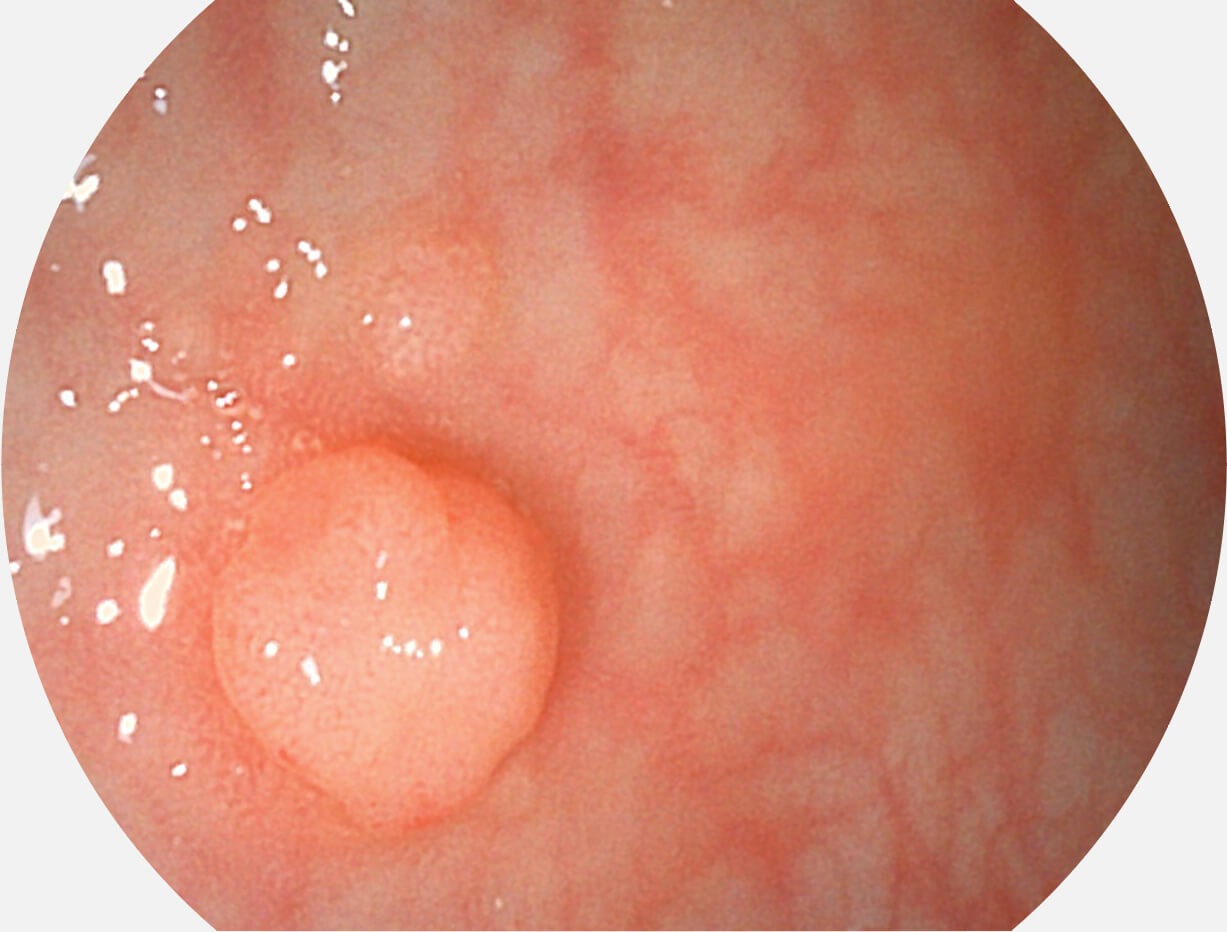

VIST图像